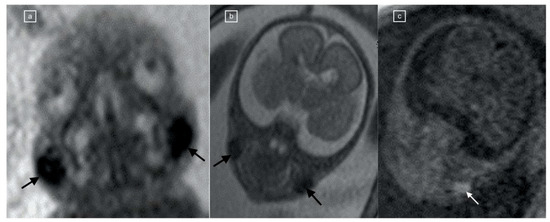

The BFS was present in 107/167 (64%) scans on at least one of the sequences: bright on T1, dark on EPI, and dark on TRUFI, with restriction on DWI. It was not visible on HASTE sequences. A positive BFS was observed most frequently on the EPI sequence (Table 1). Concordance among sequences was as follows: Substantial agreement between TRUFI and EPI (κ = 0.68; p < 0.01); moderate agreement between TRUFI and T1 (κ = 0.53; p < 0.01) as well as T1 and EPI (κ = 0.53; p < 0.01), and fair agreement between EPI and diffusion (κ = 0.28; p < 0.01) (Figure 5).

Figure 5.

(a–f) Categorized histograms for demonstrating agreement among the different sequences. TRUFI and EPI (c) demonstrated substantial agreement (κ = 0.68; p < 0.01); TRUFI and T1 (a) and T1 and EPI (e) demonstrated moderate agreement (κ = 0.53; p < 0.01); EPI and diffusion (f) demonstrated fair agreement (κ = 0.28; p < 0.01).